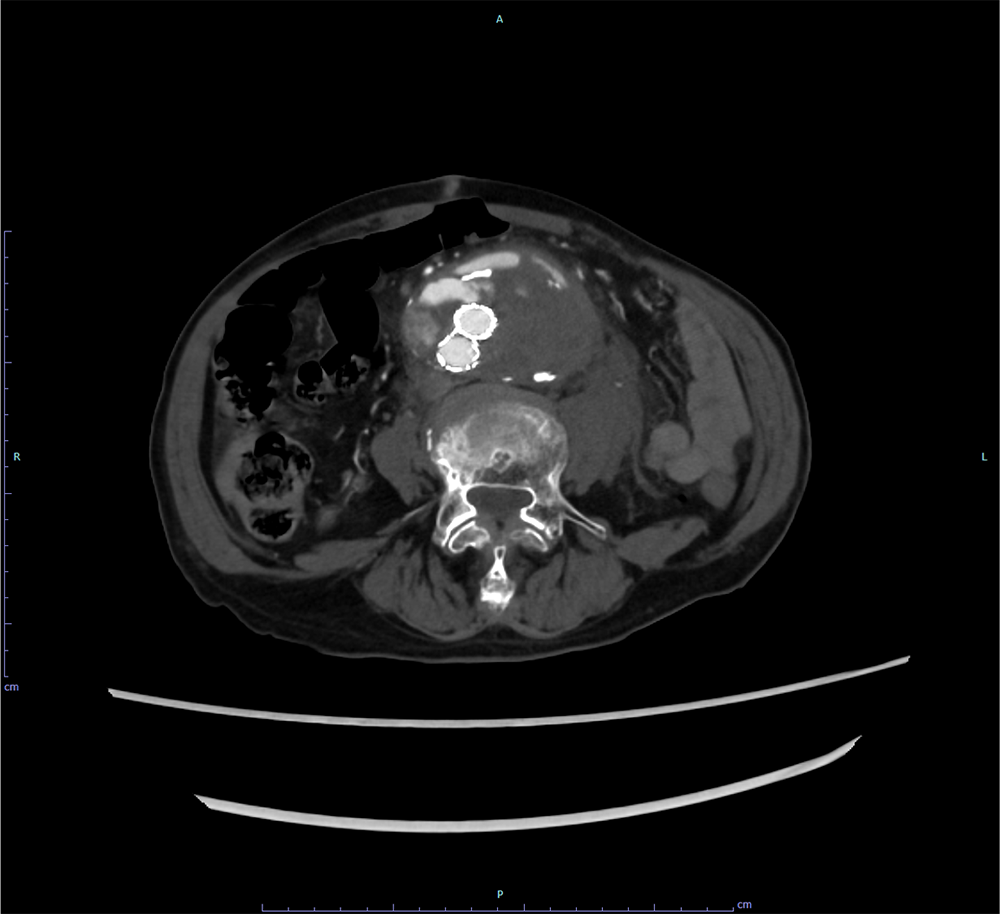

EVAR後の腹部大動脈瘤破裂に対し追加EVARを施行した一例

90歳代、男性、39kg、腹部大動脈瘤破裂

現病歴:当科で腹部大動脈瘤に対しEVAR後、増大傾向がありフォローアップされていた。急激な腹痛で前医受診、CTにて腹部大動脈瘤破裂が疑われ当科紹介となる。

当科で腹部大動脈瘤に対しEVAR術後、瘤増大傾向で外来フォローアップされていた。急激な腹痛で来院し造影CTが撮影された。瘤内にType1aエンドリークを認めるほか、瘤内解離、破裂を認めた。緊急で追加EVARが行われ、治療後エンドリークは消失し、術後経過も問題なく退院となった。